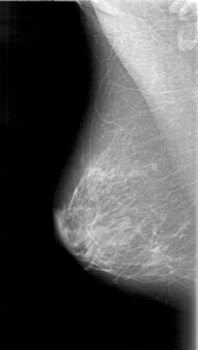

D_4024_1.RIGHT_MLO

RIGHT_MLO LINES 5236 PIXELS_PER_LINE 2956 BITS_PER_PIXEL 12 RESOLUTION 43.5 NON_OVERLAY